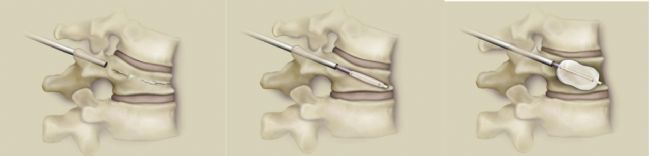

人們都希望擁有健康的骨骼,因為骨科疾病會嚴(yán)重影響到日常的生活質(zhì)量,其中椎體壓縮性骨折總是給人們帶來劇烈的疼痛感。骨質(zhì)疏松性椎體壓縮性骨折( OVCF) 患者常表現(xiàn)為腰背疼痛、脊柱畸形等,對患者的正常生活造成不良影響。經(jīng)皮椎體成形術(shù)( PVP) 是臨床治療OVCF 的主要手段,主要通過注入

骨水泥撐起塌陷椎體,幫助恢復(fù)患者的傷椎高度,使骨折得以穩(wěn)定,緩解患者的疼痛以及臨床癥狀,該成形術(shù)利于患者早期康復(fù),提高患者生活質(zhì)量⁽¹⁾。

經(jīng)皮椎體成形術(shù)(PVP)示意圖

研究表明⁽²⁾,PVP術(shù)中注入骨水泥后能夠有效維持椎體穩(wěn)定性,還能夠產(chǎn)生熱效應(yīng)將椎體末梢神經(jīng)細胞殺滅,并阻斷疼痛感覺神經(jīng)傳導(dǎo),從而減輕患者的疼痛,有利于患者術(shù)后早日康復(fù)。但在PVP術(shù)后,部分患者會出現(xiàn)骨水泥滲漏,壓迫神經(jīng),對機體神經(jīng)功能造成影響。情況嚴(yán)重的還會導(dǎo)致患者癱瘓,降低患者生存質(zhì)量,影響患者預(yù)后⁽³⁾。因此,需要不斷研發(fā)更有效更安全的骨水泥。